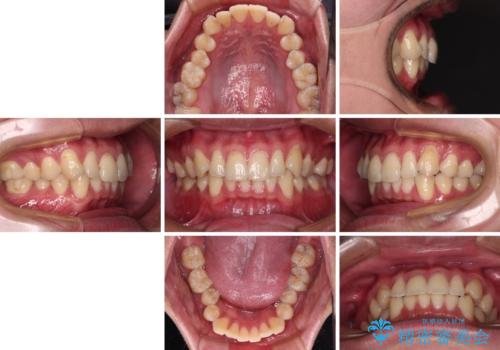

上下のデコボコを治したい インビザラインによる矯正治療

- 前歯のデコボコと突出感を気にして来院された患者様です。

極力目立たない装置を希望とのことで、インビザラインを用いて非抜歯で矯正治療を行うこととしました。

事前に親知らず4本を抜歯し、多少歯列を後方に移動できるように準備をした上で、なるべく歯と歯の間を削ることなくデコボコを解消できるように計画しました。